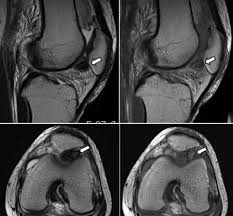

Knee Muscle Anatomy Mri - Mri Knee Anatomy Anatomy Drawing Diagram

Magnetic resonance imaging (mri scan):

Free cross sectional anatomy of the knee based on mri : To begin, we use a coronal scan of a left knee. This mri knee sagittal cross sectional anatomy tool is. Has stock or stock options held in conformis inc.; Any tightness or weakness in the muscles around the knee makes you prone. Master leg and knee anatomy using our topic page. The muscles of the knee include the quadriceps, hamstrings, and the muscles of the calf. This webpage presents the anatomical structures found on knee mri. Related posts of knee muscle anatomy mri muscle anatomy buttocks. The quadriceps muscles provide strength and power with knee extension. Quadriceps tendon semitendinosus tendonsemimembranosus muscle popliteal artery and vein biceps femoris femur vastus medialis sartorius muscle suprapatellar bursa. Involved early gray = muscle: Tips to keep joints healthy.

Scroll using the mouse wheel or the arrows. Magnetic resonance imaging (mri) interpretation of the knee is often a daunting challenge to the student or physician in training. Has stock or stock options held in conformis inc.; 1 november 2002 mri anatomy of the knee and shoulder james y. Click now to learn more about the bones, muscles, and soft tissues of these regions at leg and knee anatomy: This mri knee cross sectional anatomy tool is absolutely free to use. Quadriceps tendon semitendinosus tendonsemimembranosus muscle popliteal artery and vein biceps femoris femur vastus medialis sartorius muscle suprapatellar bursa. The knee joint is the junction of the thigh and leg. This mri knee sagittal cross sectional anatomy tool is. Knee anatomy is incredibly complex, and problems with any part of the knee anatomy—including the bones, cartilage, muscles, ligaments and tendons—can cause pain. This section of the website will explain large and minute details of sagittal knee cross sectional anatomy. Free cross sectional anatomy of the knee based on mri : Articular surface of patella and femur, condyle, epicondyle and muscles (popliteus anatomy of the ankle and foot in mri:

Has stock or stock options held in conformis inc.; This webpage presents the anatomical structures found on knee mri. The knee joint is the junction of the thigh and leg. Involved early gray = muscle: Scroll using the mouse wheel or the arrows. View of the anatomical labels. Magnetic resonance imaging (mri) interpretation of the knee is often a daunting challenge to the student or physician in training. Want to learn more about it? Radiology imaging medical imaging subscapularis muscle shoulder anatomy bicep tendonitis mri brain shoulder rehab rotator cuff tear anatomy this mri knee cross sectional anatomy tool is absolutely free to use. Abnormal anatomy with normal signal. This mri knee cross sectional anatomy tool is absolutely free to use. Learn about the muscles, tendons, bones, and ligaments that comprise the knee joint anatomy. And has received research or institutional.